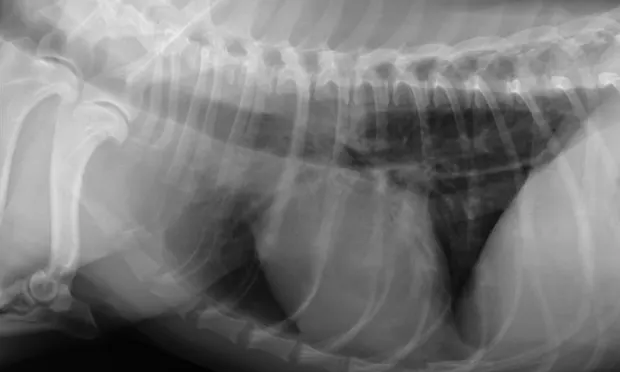

The most common cause of motility disorders is idiopathic disease, either congenital or acquired. Acquired disease may be caused by hypoadrenocorticism, esophagitis, lead toxicity, organophosphate toxicity, or myasthenia gravis (Figure 1). Hypothyroidism may be associated with a motility disorder; however, a definitive relationship has not been established.

Plain thoracic and cervical radiography is the initial diagnostic step. Radiographs can help identify megaesophagus (focal or generalized), foreign body, or paraesophageal tumor. In addition, the lungs can be evaluated for signs of aspiration pneumonia.

If no abnormalities are noted, a contrast esophagram should be considered. Use of fluoroscopy during the esophagram greatly enhances the evaluation of esophageal motility. Contrast can help identify strictures, radiolucent foreign bodies, or mass lesions. Generally, contrast esophagrams are contraindicated in patients with megaesophagus because of the high risk for barium aspiration. Esophagoscopy may be needed in some cases to assess for esopha­gitis or esophageal neoplasia (Figure 2).

If generalized megaesophagus or esophageal dysmotility is noted, further diagnostic assessment is indicated for possible underlying causes. This includes acetylcholine receptor antibody testing for myasthenia gravis, the ACTH stimulation test for hypoadrenocorticism, and measurement of serum lead levels. Although it is uncertain whether hypothyroidism causes megaesophagus, clinicians can screen for it by testing free thyroxine (T4) concentration by equilibrium dialysis. Clinicians should be cautious, however, about interpreting thyroid function tests, particularly total T4 concentrations, in these patients because of the likelihood of euthyroid sick syndrome from nonthyroidal illness, especially in cases with aspiration pneumonia.